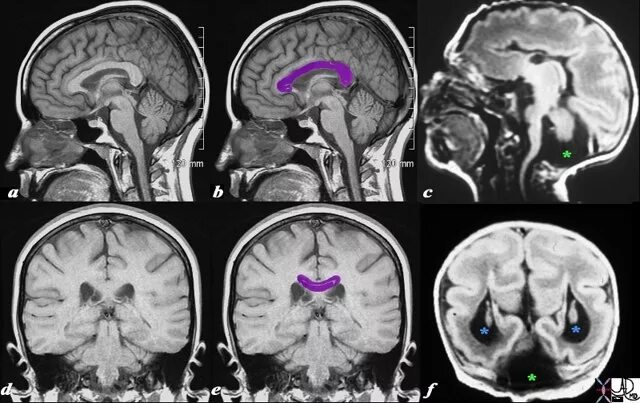

Денди уокера мрт